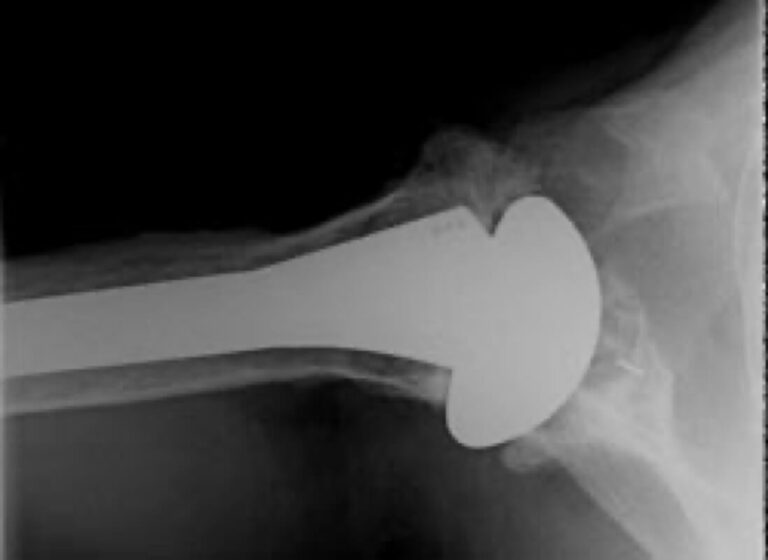

DePuy, HRP